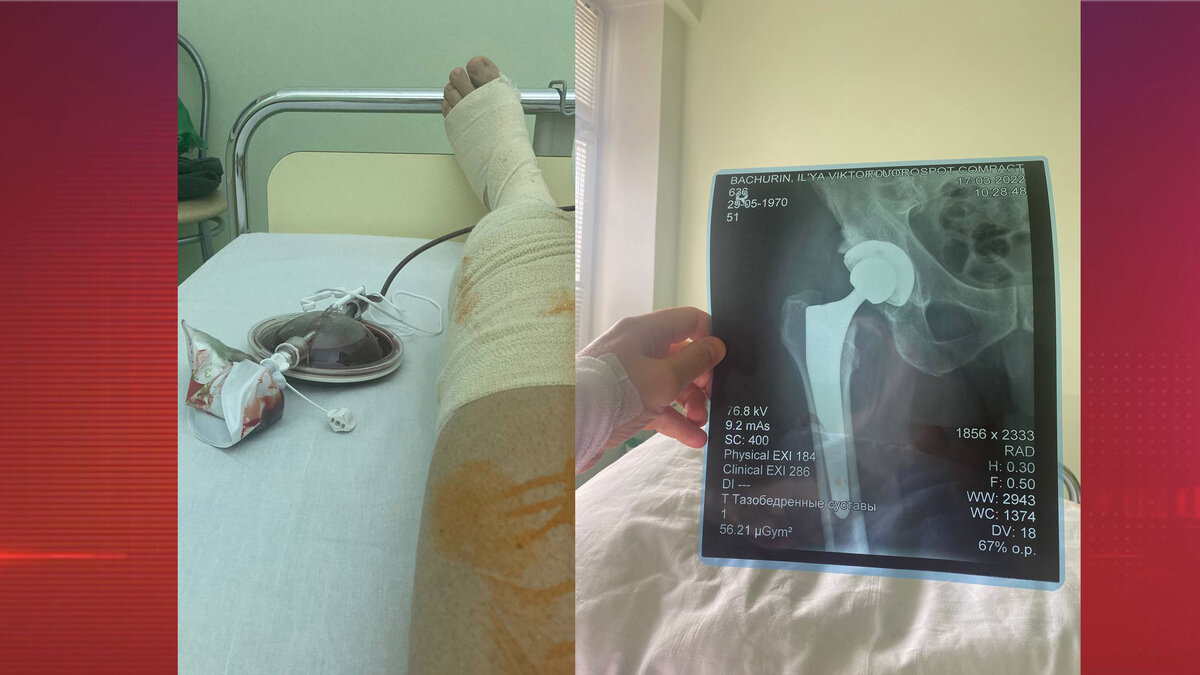

Еще недавно сооснователь «Главкино» мог передвигаться только при помощи трости. Теперь же за ним не угнаться.

Сооснователь «Главкино» Илья Бачурин рассказал о проблемах со здоровьем. Оказалось, он несколько лет мучился из-за болей в ноге и постоянно откладывал лечение. Однако когда дело дошло до того, что знаменитость самостоятельно передвигаться не мог и стал пользоваться тростью, пришлось решиться на операцию.

«Несколько лет откладывал, но пришлось сделать тяжелую операцию. Спасибо врачам Научно-медицинского центра МГУ за профессионализм и вложенную в работу душу! Три недели — и я на колесах», — поделился Бачурин в своем Telegram-канале.

Сооснователь «Главкино» быстро пошел на поправку и уже смог даже проехаться по парку на скейтборде.